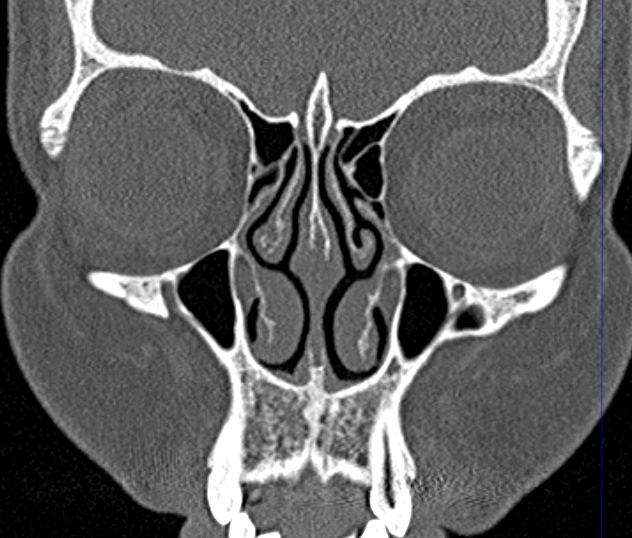

Золотым стандартом в диагностике патологических процессов пазух носа является мультиспиральная компьютерная томография, которая является быстрым безболезненным и неинвазивным (то есть без вмешательства в организм) способом исследования состояния синусов. Метод основан на проникающей способности ионизирующего излучения и получения изображений органов и тканей организма за счет разной степени поглощения ими рентгеновских лучей.

На основе полученных данных цифровые приложения томографов создают трехмерные реконструкции пазух носа, что позволяет оценить пространственное взаимоотношение анатомических структур и помогает в диагностике патологии околоносовых пазух.

Мультиспиральная компьютерная томография дает информацию о состоянии полости носа, носовой перегородки, степени воздушности околоносовых пазух, путей дренирования синусов, состоянии слезных каналов. Сканирование позволяет оценить толщину слизистой, наличие патологического содержимого в просвете пазух (уровня «жидкости»), выявить опухолевые образования. С помощью КТ можно провести точную диагностику травматических повреждений костей лицевого черепа, определить локализацию инородных тел, попавших в полости синусов.

С помощью объемной реконструкции можно перед оперативным вмешательством увидеть особенности анатомии ЛОР-органов, определить точное расположение патологического очага по отношению к окружающим тканям. Компьютерная томография помогает в диагностике аномалий развития придаточных пазух носа, слезоотводящих каналов.